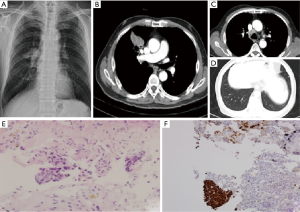

A 79-year-old man was referred to our hospital for right hilar mass on chest X-ray (Figure1A). He had taking medication for high blood pressure and diabetes mellitus. He was taken chest computed tomography (CT), there was a lobulated mass with cavity of right upper lobe anterior segment (Figure 1B). Other findings of lung were metastasis on same lobe, ipsilateral and contralateral lobe and metastatic lymphadenopathy in right highest, paratracheal, and hilar area (Figure 1C,D). Therefore, the patient was admitted for evaluation of lung mass. Endobronchial lesion was not observed on bronchoscopy. Percutaneous needle biopsy was performed in the main mass, and the result was a few atypical cell infiltration, favor squamous cell carcinoma (Figure 1E). The biopsy result was strongly suspected squamous cell carcinoma, but too small in the number of abnormal cells for confirmation. So, additional immunohistochemical study was performed. Thyroid transcription factor-1 (TTF-1) and Napsin A was negative and p63, cytokeratins (CK) 5/6 were positive, respectively (Figure 1F). These results were appropriate for squamous cell carcinoma. PET-CT was taken after histologic confirmation, hypermetabolic lesion was observed in the anterior segment of RUL with transfissural extension to right middle lobe (RML). And cavitary nodules were observed in right lower lobe (RLL) and both upper lobe (BUL), and glucose metabolism of these lesions was increased. Increased glucose metabolism was also observed in the multiple lymph nodes. We recommended patient to undergo chemotherapy, however he refused it and received only conservative therapy.